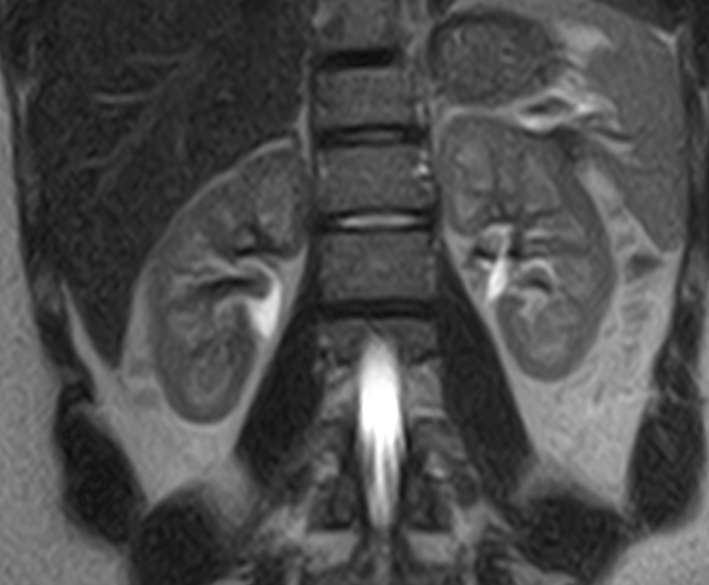

Мочеточники — это парные трубчатые органы, длиной приблизительно 25-30 см, соединяющие почечные лоханки с мочевым пузырем. Наиболее частой патологией является нарушение оттока мочи по мочеточнику за счет сужения (стриктуры) или обтурации (полной закупорки) его просвета.

Магнитно-резонансная томография позволяет получить информацию о состоянии мочеточников и окружающих мягких тканей для точной диагностики заболеваний данной анатомической области.

В клинике «Доступная медицина» исследование проводится с помощью высокотехнологичного оборудования — 32-канального высокопольного томографа новейшего поколения TOSHIBA VANTAGE TITAN 1,5 Тесла. Аппарат послойно сканирует структуры исследуемого органа и на основе полученных данных реконструирует трехмерные изображения превосходного качества.

В первую очередь необходимо отметить, что магнитно-резонансная томография мочеточников выполняется в комплексном обследовании почек и мочевыводящих путей, как самостоятельный метод диагностирования невозможен.

При помощи магнитно-резонансной томографии удается оценить состояние органов и выявить имеющиеся патологии:

- оценить топографическое положение и выявить аномалии развития данного органа;

- оценка кровоснажения мочеточников;

- выявить патологические очаги и имеющиеся зоны поражения в мочеточниках;

- определить наличие новообразований, его размеры;

- оценить функциональность данного органа.